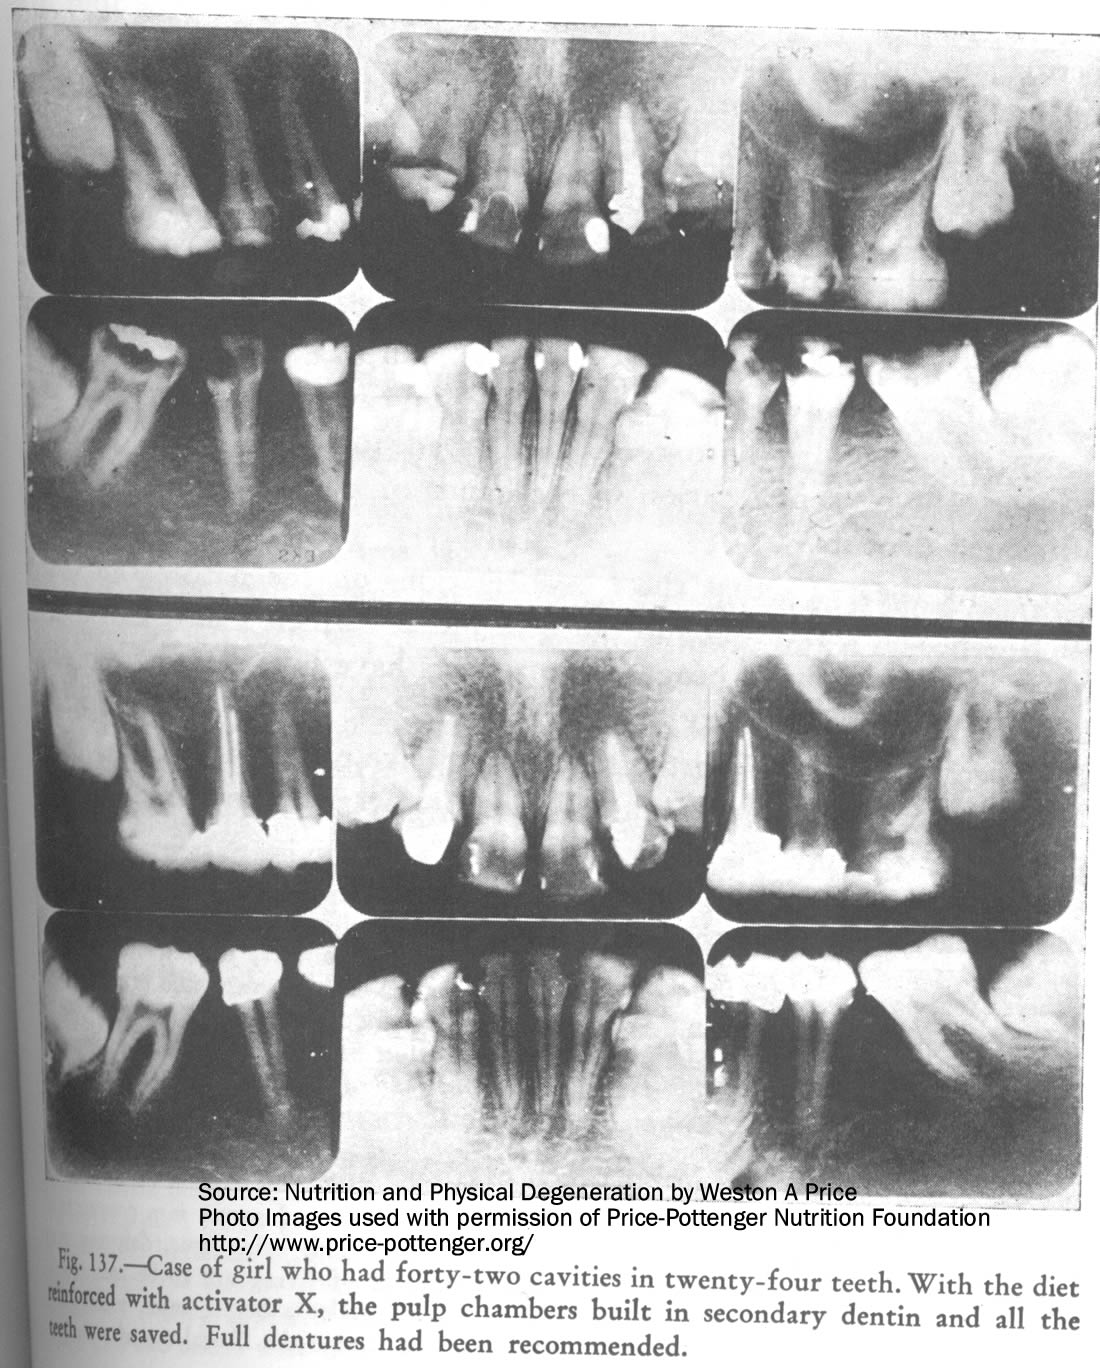

- 3). 24 ta tishida 42 ta kariyesi mavjud qiz oziqlanishni tartibga solish orqali pulpa palatalarida dentin hosil bo’kishiga va tishlarning mustahkamlanishiga erishgan. Manba: Veston Prays.